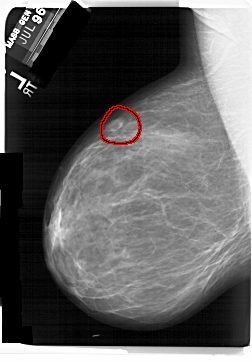

FILE: A_1408_1.LEFT_CC.OVERLAY

TOTAL_ABNORMALITIES 1

ABNORMALITY 1

LESION_TYPE MASS SHAPE OVAL MARGINS CIRCUMSCRIBED

ASSESSMENT 4

SUBTLETY 4

PATHOLOGY BENIGN

TOTAL_OUTLINES 1

BOUNDARY